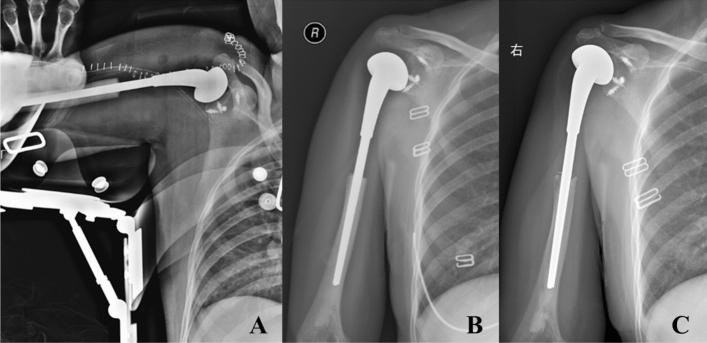

The purpose of this study was to evaluate the functional results, complications and related factors of prosthesis reconstruction after malignant tumor resection of primary proximal humeral, and also evaluate whether soft tissue reconstruction with mesh patch and anchors can improve clinical results. From 2002 to 2016, forty-one patients were enrolled in this study. The pathological diagnosis contained 27 cases of osteosarcoma, 7 cases of chondrosarcoma and other primary malignant bone tumors. Both mesh patch and anchors were used in the reconstruction of joint capsule and the surrounding soft tissues in 27 cases. The mean postoperative follow-up was 60.6 months. The average active abduction angle and passive abduction angle was 33.5 (5-71) degrees and 72.4 (52-104) degrees. The prosthetic humeral head displacement was over 2 cm in 5 cases (12.2%). The average MSTS score was 23.1. The overall 5-year survival rate of prosthesis was 88.2%. The length of osteotomy, whether preserving deltoid muscle, whether applying mesh patch and anchors had significant effects on the abduction angle of shoulder joint; the length of osteotomy, whether applying mesh patch and anchors had significant effects on the degree of upward displacement of prosthesis. The application of both mesh patch and anchors in prosthesis reconstruction achieved more stable result and better function of shoulder joint. To ensure the stability of shoulder joint and the firm wrapping of surrounding soft tissue are key factors affecting the postoperative function.

本研究旨在评估原发性肱骨近端恶性肿瘤切除后假体重建的功能结果、并发症及其相关因素,并评估网片和锚钉的软组织重建是否能改善临床结果。2002 年至 2016 年间,共纳入 41 例患者。病理诊断包括 27 例骨肉瘤、7 例软骨肉瘤等原发性恶性骨肿瘤。27 例患者同时使用网片和锚钉修复关节囊和周围软组织。术后平均随访 60.6 个月。术后平均主动外展角度和被动外展角度分别为 33.5(5-71)度和 72.4(52-104)度。5 例(12.2%)假体肱骨头移位超过 2cm。平均 MSTS 评分为 23.1。假体 5 年总体生存率为 88.2%。截骨长度、是否保留三角肌、是否应用网片和锚钉对肩关节外展角度有显著影响;截骨长度、是否应用网片和锚钉对假体向上移位程度有显著影响。假体重建中同时应用网片和锚钉可获得更稳定的结果和更好的肩关节功能。确保肩关节的稳定性和周围软组织的牢固包裹是影响术后功能的关键因素。